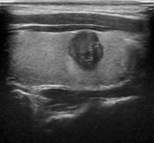

Figure 6 illustrates the segmentation outcomes attained with different neural networks using the same dataset. The enhanced U-Net network proposed in this study is evaluated alongside expert gold standards, Swin-Unet, U-Net, and other well-known network models. The segmentation results from the Swin-Unet network show jagged edges and less smooth nodule edge segmentation, leading to suboptimal outcomes. In the case of U-Net, there are evident under-segmentations with significant discrepancies in the segmented area of some nodules, resulting in inaccurate segmentation results. However, the use of the improved U-Net network introduced in this research produces smoother edges of the segmented thyroid nodules, and the edge contours more closely align with those of the expert gold standard. Moreover, the errors in shape and segmented area are smaller compared to those seen with U-Net and Swin-Unet. The findings suggest that the improved U-Net network provides superior performance in thyroid nodule segmentation.

Draft Xu 795668614-image6.png

(a) Original image

Figure 6. Ultrasound image segmentation results of thyroid nodules using different networks